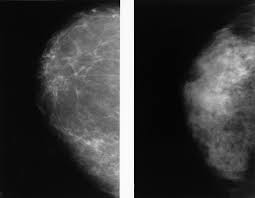

Invasive breast cancer can appear as a white patch or mass on a mammogram. The tumor cells don't stay within the clear borders of the mass, but instead invade the nearby breast tissue. You may notice dimpling or pitting, and the skin on your breast. A rash isn't the only visual symptom of inflammatory breast cancer. Regular mammograms are the best tests doctors have to find breast cancer early. In a normal breast, a mammogram shows normal skin dark grey fat and lighter grey breast tissue. According to the american cancer society (acs), the most common sign of breast cancer is a new lump or mass in the breast. How can mammograms be used? Cancers may be seen as masses (like a ball, but usually with an irregular shape), areas of asymmetry that resemble normal tissue, calcifications (white specks), and/or areas of architectural distortion (imagine the puckering caused by pulling a thread in a piece of fabric). In this mammogram image, the breast calcifications are in ductal patterns. Healthy mammograms can still vary in appearance. It is important to bear in mind that most women who are asked to come back after. Any area that does not look like normal tissue is a possible cause for concern.

Invasive breast cancer can appear as a white patch or mass on a mammogram. Often, you might not feel a lump, even if it is there. Regular mammograms are the best tests doctors have to find breast cancer early, sometimes up to three years before it can be felt. The appearance of normal breast tissue on a mammogram varies from person to person, and no two mammograms look the same. Mammograms provide a look inside the breast to help doctors (radiologists) detect breast cancer, often in the early stages when it's most treatable.

Ai Assisted Radiologists Can Detect More Breast Cancer With Reduced False Positive Recall Imaging Technology News from www.itnonline.com Breast cancer and some noncancerous (benign) breast conditions can appear white on a mammogram. By the time it's diagnosed, it usually has grown into the skin of your breast. The outer edges of these cells look fuzzy or spiky (called spiculated). They will look carefully at the mammogram to interpret the results. The doctor reading your mammogram will be looking for different types of breast changes, such as small white spots called calcifications, larger abnormal areas called masses, and other suspicious areas that could be signs of cancer. The appearance of normal breast tissue on a mammogram varies from person to person, and no two mammograms look the same. Cancers may be seen as masses (like a ball, but usually with an irregular shape), areas of asymmetry that resemble normal tissue, calcifications (white specks), and/or areas of architectural distortion (imagine the puckering caused by pulling a thread in a piece of fabric). According to the american cancer society (acs), the most common sign of breast cancer is a new lump or mass in the breast.

This is considered an abnormal mammogram, but not necessarily one that's indicative of cancer. The tumor cells don't stay within the clear borders of the mass, but instead invade the nearby breast tissue. The appearance of normal breast tissue on a mammogram varies from person to person, and no two mammograms look the same. Dr sarah jarvis mbeif a mammogram is abnormal, further tests will be needed. The doctor reading your mammogram will be looking for different types of breast changes, such as small white spots called calcifications, larger abnormal areas called masses, and other suspicious areas that could be signs of cancer. Regular mammograms are the best tests doctors have to find breast cancer early, sometimes up to three years before it can be felt. Mammograms will often detect areas that are more dense than normal breast tissue or that have little flecks of calcium within milk ducts. What does breast cancer look like on a mammogram? What does breast cancer look like on a mammogram? You may notice dimpling or pitting, and the skin on your breast. This can make it harder for your radiologist to spot signs of breast cancer, since dense tissue and tumors both look white in mammogram images. Any area that does not look like normal tissue is a possible cause for concern. Any area that does not look like normal tissue is a possible cause for concern.